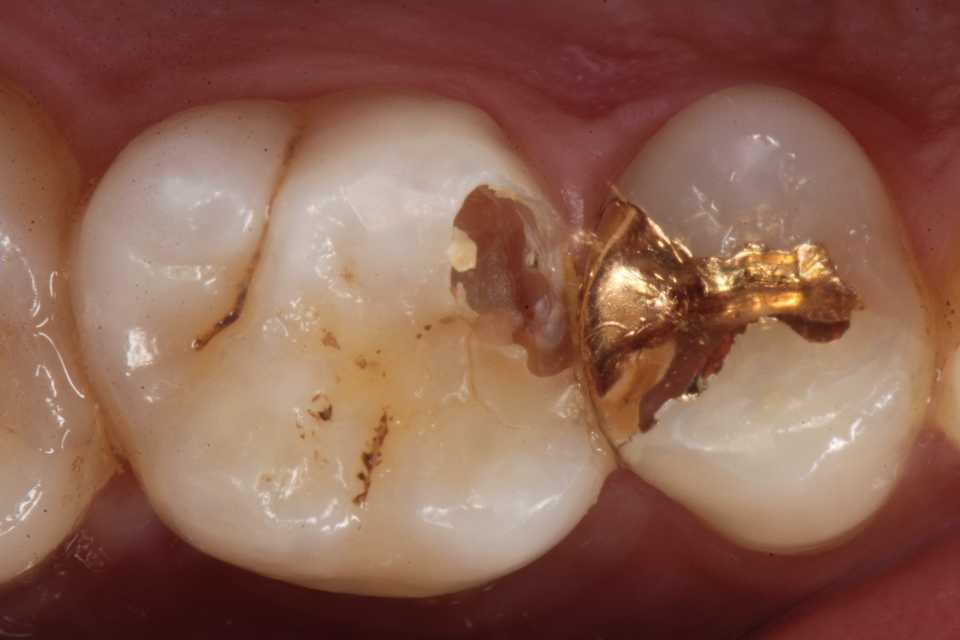

30代男性、右上6、隣接面カリエス、CR充填後(当院ではない)の2次カリエス、外傷性咬合(食いしばり)有り

今日は、10ヶ月程前に時間がないのでα-TCPで仮充填しておいた歯の治療の続き。

とりあえずα-TCPを除去し始めたが内部の象牙質は硬化している。虫歯はα-TCPで治る。

再度3MIX+α-TCPで覆罩してCR充填した。

歯肉縁下に虫歯やクラックが及んでいたができる限り取り除いた。歯肉側のエナメル質は取らざるを得なかったが、これ以上取ると大穴が開く寸前までいった。象牙質のクラックが少し見えるが、α-TCPで治って欲しい。

では時系列でどうぞ

頬側の虫歯は追求するしかない。

難しかったので途中経過を撮る余裕がなかった。